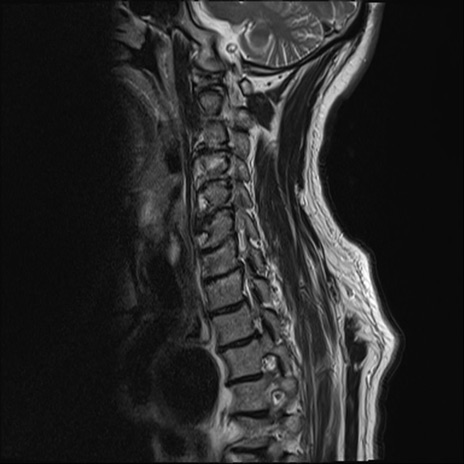

【整形】TIPS症例7 頚椎MRI T2WI(矢状断像)

頚椎MRI

T2WI(横断像)

矢状断像と横断像